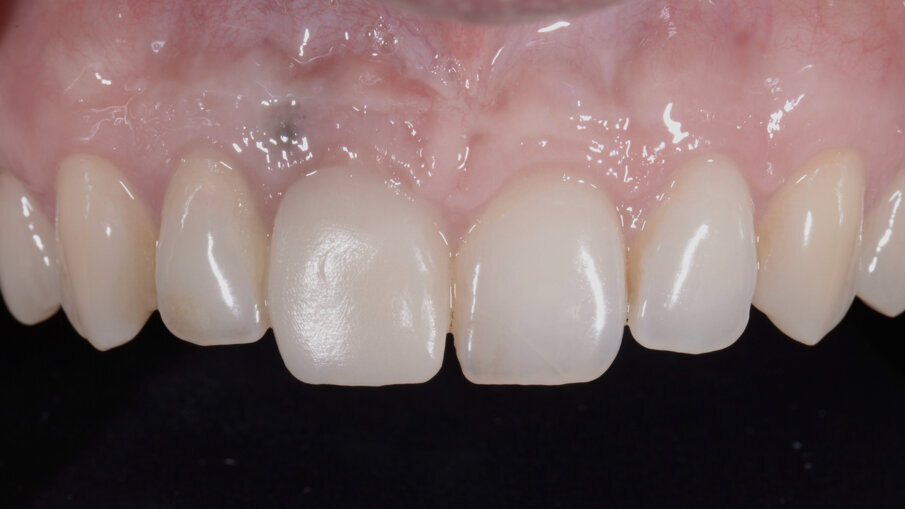

Trascorsi quattro mesi, ad avvenuta osteointegrazione dell’impianto, il condizionamento dei tessuti appariva ottimale sia in termini di qualità dei tessuti sia in termini di volume rigenerato. I profili gengivali erano perfettamente armonici e naturali grazie al provvisorio (Fig. 29). A questo punto, dopo avere svitato il provvisorio dall’impianto, ho copiato con lo scanner intra-orale la posizione delle papille e della parabola gengivale. In tal modo, creando la cosiddetta “Maschera gengivale”, ho condiviso con il software le informazioni morfologiche necessarie per realizzare i manufatti protesici definitivi (Figg. 30, 31).

Fig. 28_Guarigione dopo 4 mesi.

Fig. 29_Aspetto dei tessuti condizionati dopo la rimozione del provvisorio.